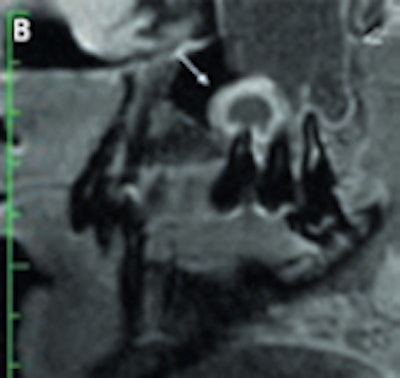

"MRI of the dental apparatus is technically challenging as the bony structures of the mandible and teeth give only little or no MR signal," Rohde said. "Another concern is the problem of air content and metal artifacts in the oral cavity that limit the use of MRI in this special setting. As a principal finding of our experiments, MRI proved to be superior to MDCT [multidetector-row CT] and to CBCT in visualizing periodontal structures like the periodontal space and the adjacent lamina dura. Surprisingly, even cortical and trabecular bone were displayed better with MRI than with MDCT and CBCT. Therefore, I believe that MRI could become an important complementary imaging source of the jaw and teeth apparatus in pathologies of tissue investing and supporting the teeth."

An example of cone-beam CT. In this instance, the lower left third molar (d. 38) was imaged after panoramic radiograph with CBCT. The arrows mark the mandibular canal. Images courtesy of Dr. Anni Suomalainen.